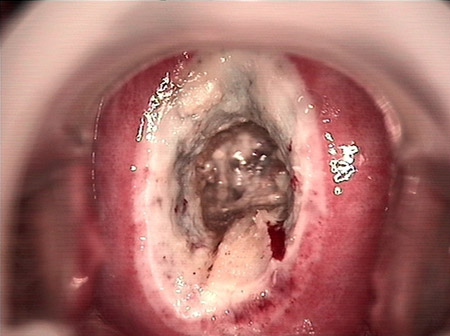

• CIN 2-3 碘著色后CIN 2-3 碘著色后

• CIN 2-3 leep術(shù)后CIN 2-3 leep術(shù)后